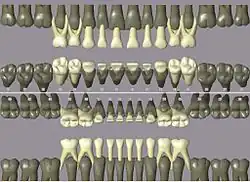

У человека прорезываются 20 молочных зубов: по 10 на верхней и нижней челюстях, по 5 на каждой половине челюсти (два резца, клык и два моляра).

Схема прорезывания и выпадения молочных зубов:

Верхняя челюсть:

| Название зуба | Прорезывание, мес. | Выпадение, лет |

|---|---|---|

| Центральные резцы | 8-12 | 6-7 |

| Боковые резцы | 9-13 | 7-8 |

| Клыки | 16-22 | 10-12 |

| Моляры | 25-33 | 10-12 |

Нижняя челюсть

| Название зуба | Прорезывание, мес | Выпадение, лет |

| Центральные резцы | 6-10 | 6-7 |

| Боковые резцы | 10-16 | 7-8 |

| Клыки | 17-23 | 9-12 |

| Моляры | 23-31 | 10-12 |